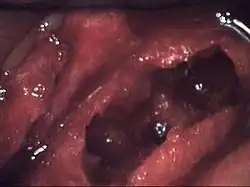

Osteonecrosis of the jaw of the upper left jaw in a patient diagnosed with chronic venous insufficiency